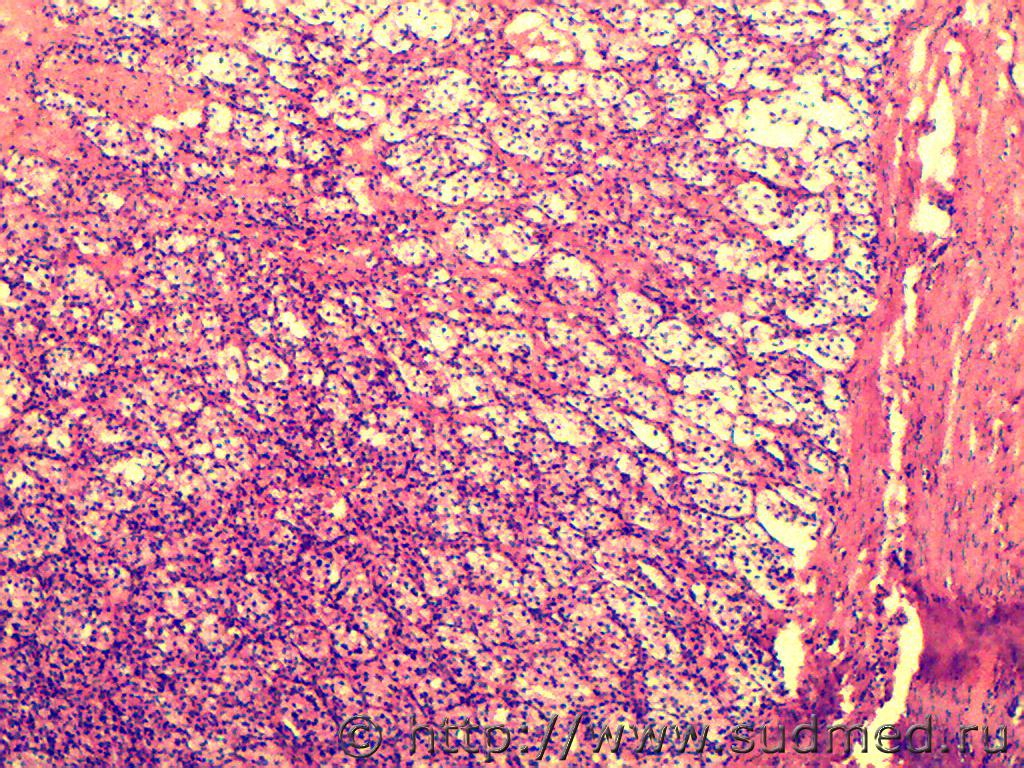

Вторые две: пневмоцистная пневмония, ГЭ, по Grocott не красим